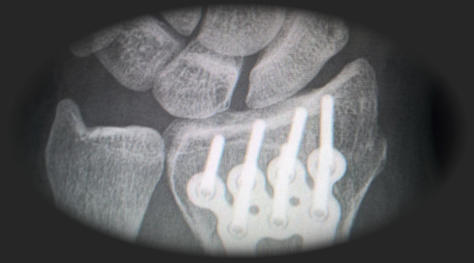

Nach einem Arbeitsunfall sind wir für Sie da.

Ambulante Reha der Berufsgenossenschaft Anders als Fahrten zu ambulanten Behandlungen bei niedergelassenen Ärzten, sind Fahrten zu Ihrer Behandlung oder Untersuchung durch die Berufsgenossenschaft ohne vorherige Genehmigunng möglich. Erforderlich ist lediglich die Verordnung der Fahrten durch den Arzt oder die Unfallbehandlungsstelle. Es fällt kein Eigenanteil, oder sonstige durch Sie zu tragende Kosten, für die verordneten Fahrten an. Konzentrieren Sie sich auf Ihre Behandlung, den Rest machen wir. Bei Fragen und für Bestellungen erreichen Sie uns unter: Telefon: 0421 377 07 800 per Email unter: Info@Bremer-Taxi.de Kontaktdaten der Unfallbehandlungsstelle Bremen BG Ambulanz Bremen Industriestr. 3 28199 Bremen Tel.: 0421 59 86 06 0 Email: Info@BGA-Bremen.de Stationäre Behandlung der Berufsgenossenschaft Wie auch bei ambulanten Behandlungen, fällt bei Fahrten zu stationärenBehandlungen durch die Berufsgenossenschaft kein Eigenanteil an. Erforderlich ist auch hier lediglich die Verordnung durch Ihren Arzt oder die Unfallbehandlungsstelle. Kontaktdaten des BG Klinikums Hamburg (Boberg) BG Klinikum Hamburg Bergedorfer Str. 10 21033 Hamburg Tel.: 040 73 06 0 Email: Mail@BGK-Hamburg.de Bei Fragen und für Bestellungen erreichen Sie uns unter: Telefon: 0421 377 07 800 oder per Email unter: Info@Bremer-Taxi.de

Ambulante Behandlung Nach einem Wege- oder Arbeitsunfall findet die ambulante Behandlung meistens in der ambulanten Unfallbehandlungsstelle der BG in Bremen statt. Wir holen Sie entsprechend Ihres Behandlungsplans ab. Stationäre Behandlung Stationäre Behandlungen durch Ihre Berufsgenossen- schaft finden oftmals im BG- eigenen Krankenhaus in Hamburg Bergedorf (Boberg) statt. Auch hierfür sind wir für Sie der richtige Ansprechpartner. Stationäre Rehabilitation Deutschlandweit gibt es viele Kliniken für Rehabilitation, die auch Behandlungen für die Berufsgenossenschaften anbieten. Gerne befördern wir Sie auch auf diesem Weg. Wiedereingliederung In bestimmten Fällen ist Ihre Berufsgenossenschaft bereit, Ihnen Kosten für das Taxi zu Ihrer Arbeitsstelle zu erstatten Gerne stehen wir Ihnen täglich und automatisch für die Fahrt zur Arbeitsstelle zur Verfügung.